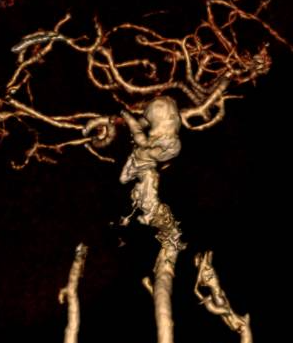

Ngay khi nhập viện, các bác sỹ nghi ngờ bệnh nhân có bất thường hệ thống mạch máu não nên đã chỉ định chụp cắt lớp vi tính mạch máu não cho bệnh nhân. Kết quả hình ảnh chụp cắt lớp vi tính mạch máu não cho thấy, bệnh nhân có túi phình lớn ở động mạch cảnh trong trái, kích thước khoảng 10 x 8 x 6 mm, khu trú tại đoạn động mạch mắt.

Hình ảnh túi phình lớn ở động mạch cảnh trong trái trên CLVT mạch máu não

Quá trình can thiệp được thực hiện qua động mạch đùi phải theo phương pháp Seldinger. Bệnh nhân được chụp mạch não để đánh giá chính xác túi phình. Ê-kíp đã đặt thành công stent chuyển dòng kích thước 4,25 × 20 mm qua cổ túi phình động mạch cảnh trong trái đoạn động mạch mắt. Hình ảnh sau can thiệp cho thấy stent áp sát thành mạch, che phủ hoàn toàn cổ túi phình, giảm rõ rệt dòng máu vào túi phình, đồng thời đảm bảo tưới máu não tốt, tuần hoàn não trước đạt TICI 3.

Hình ảnh thả stent chuyển dòng túi phình lớn ở động mạch cảnh trong trái dưới DSA